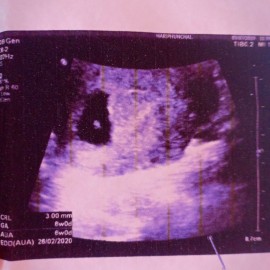

ตั้งครรภ์ 6 w แล้วมีเลือดออก แต่ไม่เยอะ ไปหาหมอหมอฉีดยากันแท้งให้ค้ะ